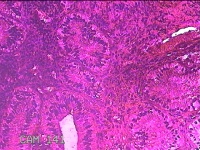

宫颈3点、6点、9点、12点组织

性别

女

年龄

38岁

临床诊断

人乳头瘤病毒感染

一般病史

发现人乳头瘤病毒感染半月。

标本名称

大体所见

1.“宫颈3点组织”:灰白暗红色组织0.8x0.7x0.2cm一块。 2.“宫颈6点组织”:灰白粉红色组织0.8x0.3x0.2cm一块。 3.“宫颈9点组织”:灰白粉红色组织0.7x0.5x0.2cm一块。 4.“宫颈12点组织”:灰白暗红色不规则碎组织1.3x1x0.3cm一堆。